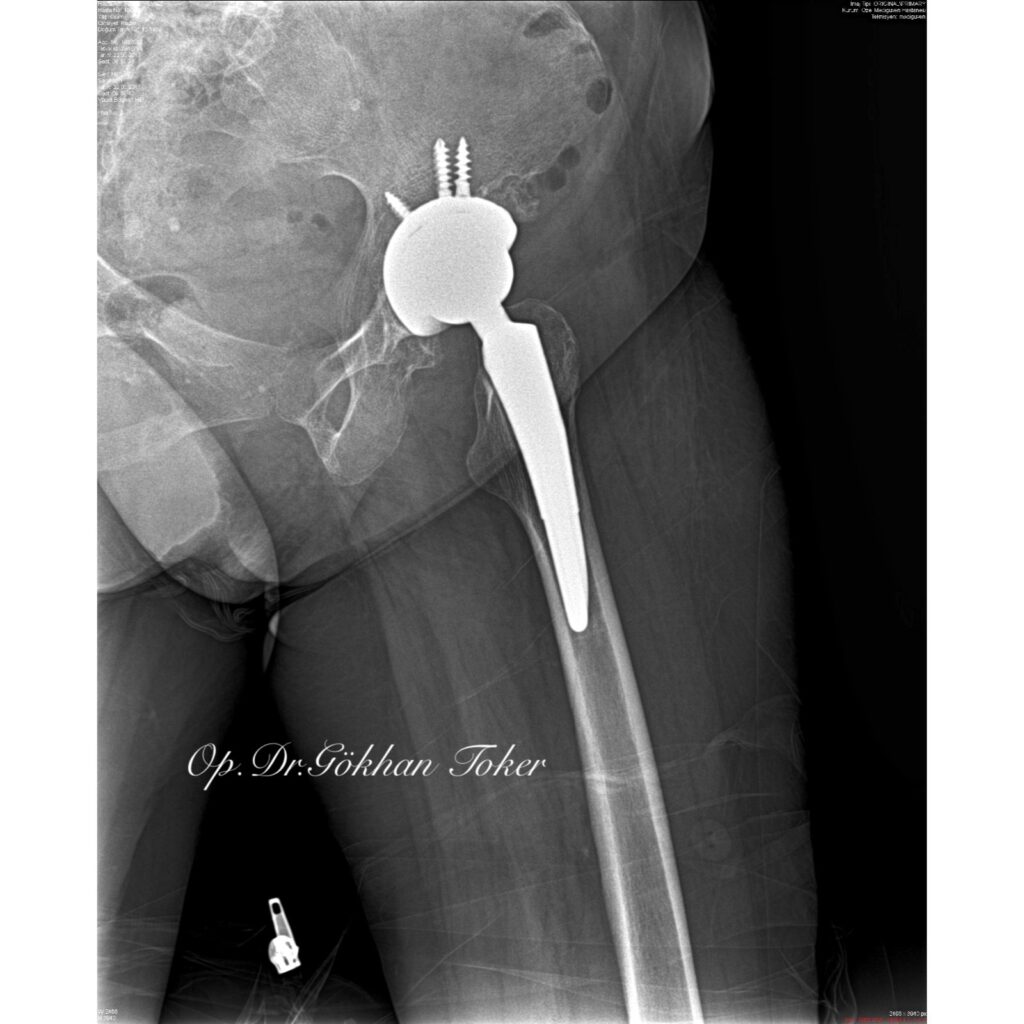

V.K.